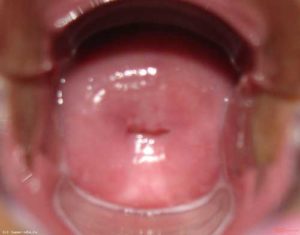

Патологические изменения эпителиального слоя шейки матки до некоторого времени никак не проявляются. Эрозия заметна при гинекологическом осмотре, но не все женщины подвергаются ему с должной регулярностью. И все-таки есть особенности, которые при внимательном отношении можно заметить и самостоятельно.

Эрозией шейки называется любое нарушение нормального физиологического состояния ее слизистых покровов. К подобным нарушениям относятся механические и химические повреждения, аномальное развитие эпителия. По характеру и причинам возникновения эрозии подразделяются на два основных вида: